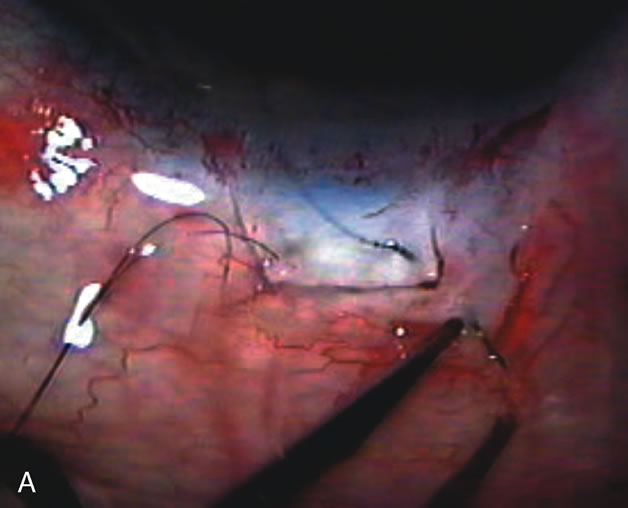

Fig. 4. Viscocanalostomy with deep sclerectomy and phacoemulsification. Nonpenetrating filtration procedures (NPFS) may be combined with phacoemulsification. Patients with mild disc damage and a history of limited topical drug therapy are the best candidates. Patients who require an IOP in the low teens are not good candidates for NPFS. By definition, NPFS is designed to lower IOP without penetrating into the anterior chamber, thereby avoiding the complications associated with trabeculectomy. Viscocanalostomy is intended to allow aqueous to percolate through a trabeculodescemetic membrane into a subscleral cavern created by the deep sclerectomy. The aqueous diffuses from the cavern into the dilated ostia of Schlemm's canal and into the episcleral venous plexus. A. Fashion a uniform 300-micron superficial scleral flap 1 mm into clear cornea. B. Construct a second 600-micron deep flap that facilitates the unroofing of Schlemm's canal, seen as the darker area. C. Use viscoelastic to dilate the ostia of Schlemm's canal. The major problem with viscocanalostomy is the eventual closure of the ostium decreasing flow to the episcleral plexus. D. Dissect the deep flap anteriorly into clear cornea creating the trabeculodescemetic membrane. This membrane is clearly seen between the scleral spur and the bend of the deep flap. The integrity of this membrane ensures the nonpenetrating portion of the surgery. Another problem with NPFS is the eventual fibrosis of this initially transparent membrane requiring goniopuncture. E. Deep sclerectomy gets its name from removal of the deep flap. Removal of this flap creates the potential subscleral space for accumulation of aqueous before it enters Schlemm's canal and exits the episcleral venous plexus. After removal of the deep flap, the superficial flap is sutured into place and conjunctiva closed. Approximately half of these procedures develop a shallow bleb.